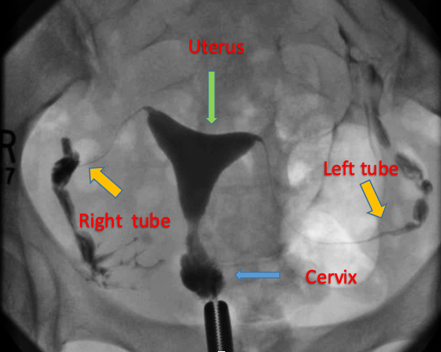

H.S.G

(हिस्टेरोसालफिंगोग्राफी)

क्ष - किरणाद्वारें गर्भाशयाची तपासणी